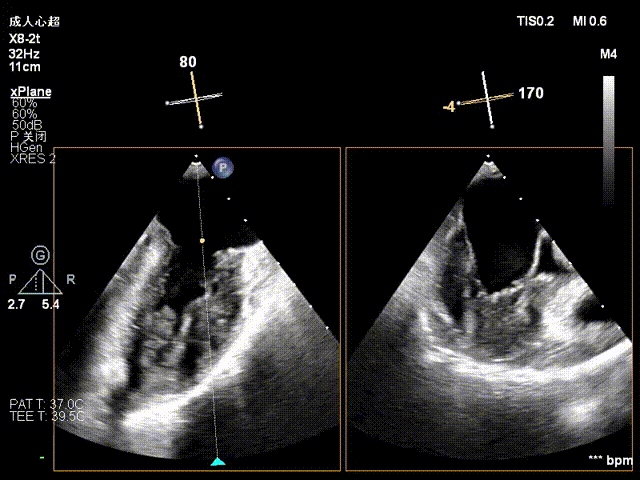

The operation was performed in a hybrid operating room and completed under the guidance of real-time three-dimensional transesophageal echocardiography (3D TEE) and X-ray fluoroscopy throughout the entire process.

Mitral Valve Repair Stage: Via the transfemoral venous approach, a 4.0 cm atrial septal puncture was performed, and one mitral valve clip was selected. The unique feature of wide-angle deployment effectively resolved the issue of excessive leaflet tension during valve clip closure. Under the precise guidance of ultrasound, one clip was successfully implanted at the site of the widest regurgitation in the A2-P2 segment of the mitral valve. Immediate postoperative TEE assessment showed that mitral regurgitation was reduced to trivial (1+), the mean transvalvular pressure gradient was only 3 mmHg, and pulmonary venous retrograde flow was significantly improved.

Atrial Septal Puncture

Guide Sheath Implantation

Mitral Clip Trajectory Test

Orientation Confirmation

Orientation Reconfirmation After Transvalvular Crossing